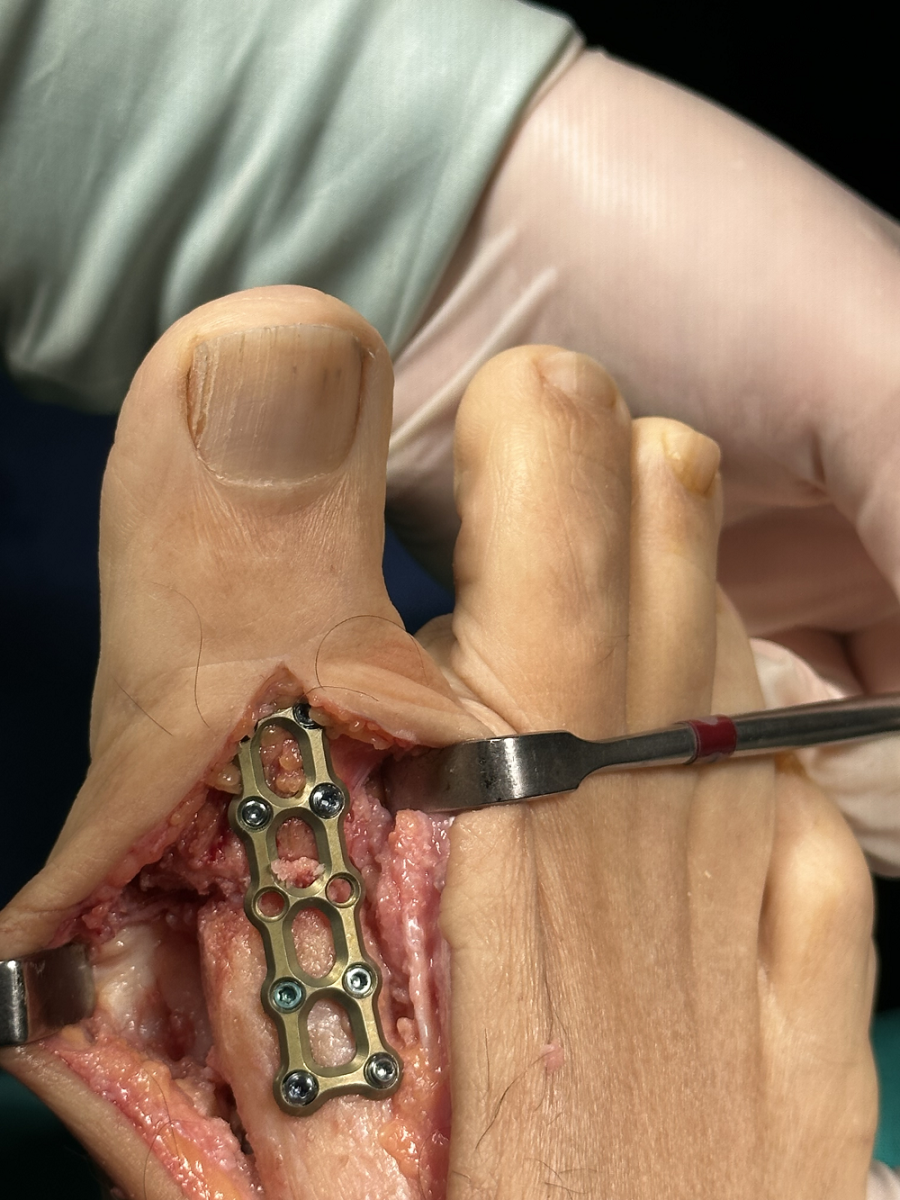

Çeilektomi ameliyatı

Artrodez: Ayak başparmağının kıkırdak hasarı ciddi olduğunda genellikle kemiklerin birbirine kaynaştırılması (artrodez) önerilir. Artrodez sırasında eklemin kalıcı bir pozisyonda sabitlenmesi için, vidalar veya plak kullanacaktır. Şiddetli halluks rijiduslu veya çeilektominin başarısız olduğu hastalarda ağrıyı azaltmanın en güvenilir yolu artrodezdir.